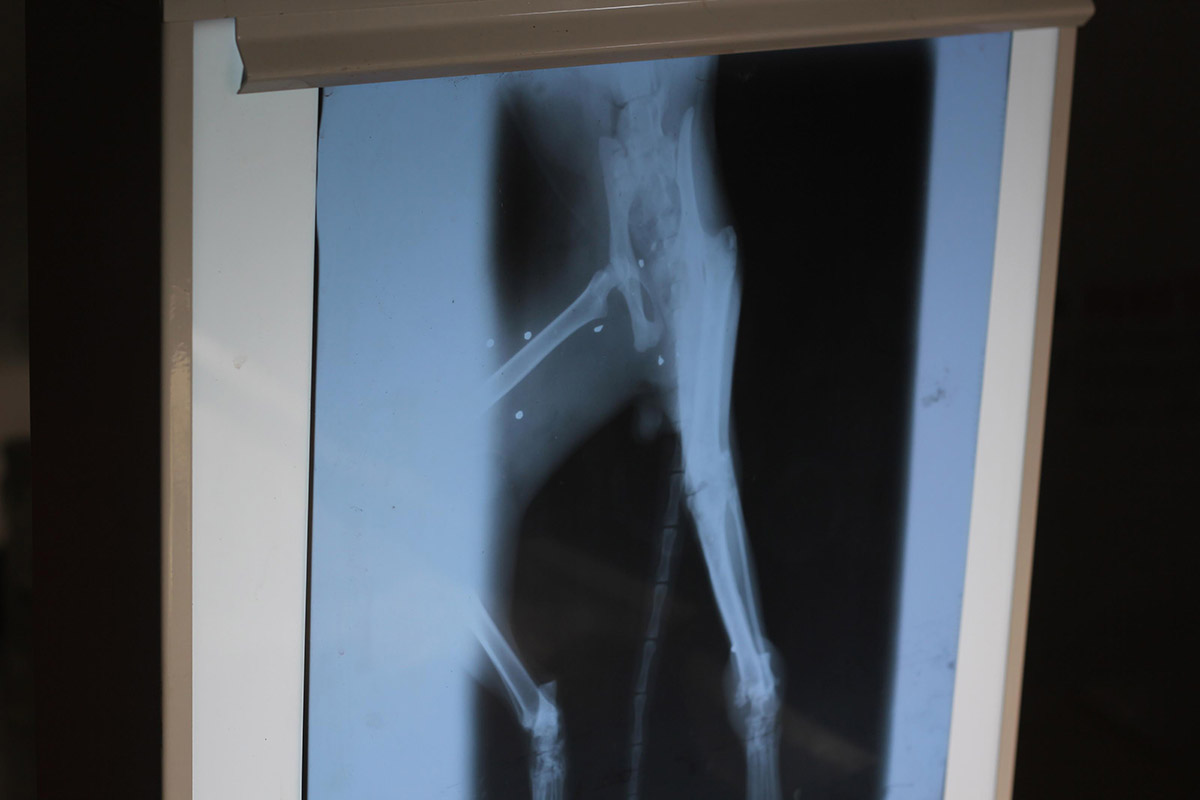

Kırık şüphesiyle HAYTAP Tedavi Merkezi'nde röntgen filmi çekilen sokak kedisinin vücudunda 7 saçma ve sol arka ayağında kırık olduğu belirlendi. Ameliyata alınan kedinin vücudundaki saçmalardan 4’ü çıkarılırken, 3'ü ise çok derinde olduğu için yerinde bırakıldı.

3 yaşlarındaki kedinin sağlık durumunun iyiye gittiğini söyleyen Veteriner Hekim Ali Laçinbala, "Kedimizin çekilen röntgen filmi sonucunda vücudunda 7 tane saçma tespit ettik. Ateşli silahla vurulmuş, 4 tanesini çıkartabildik, 3 tanesini ise çok derinlerde olduğu için bıraktık. Ayrıca sol arka ayağında bir kırık tespit ettik. Kurşun yaralarından oluşmuş enfeksiyona yönelik tedavisine devam edeceğiz. Sol arka ayağındaki kırıkla alakalı ise yine o bölgede bir enfeksiyon şekillenmiş. Enfeksiyonun kana karışarak septisemi yapmaması için şu anda oraya müdahale etmedik. İlerleyen günlerde oraya da müdahale edeceğiz. Ameliyat sırasında hayvandan gelen dışkı örneğinde de bağırsak solucanları etkenlerine rastladık. Ona yönelik de yine ilaçlama çalışmasına başladık" dedi.